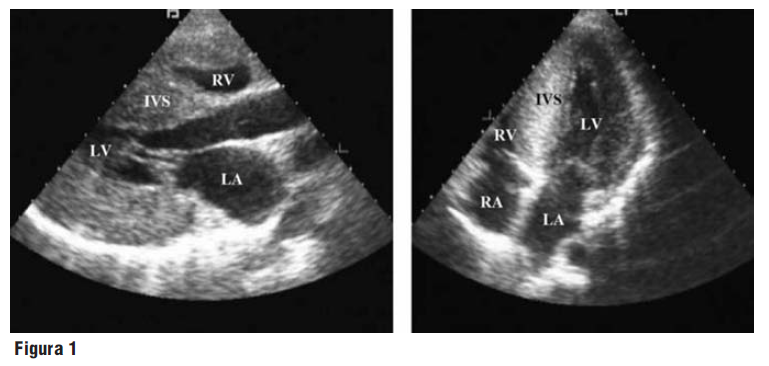

Resultado: paciente de 44 años, mujer, con antecedentes de tabaquismo y etilismo, ingresa por cuadro de dolor torácico en reposo, de inicio reciente, intermitente de hasta 15 minutos de duración, asociado a sudoración profusa y vértigo, el cual mejora con uso de dinitrato de isosorbida. Niega episodios previos. ECG de ingreso con ritmo sinusal, 70 lpm, eje QRS + 60º e inversión de onda T en pared inferior. Troponina y CK-MB masa negativas. Realizado ecocardiograma transtorácico, el mismo informa contractilidad y función biventricular preservada, dilatación de arterias coronarias derecha e izquierda en toda su extensión, siendo el origen de la coronaria izquierda en el tronco pulmonar y presentando flujo reverso coronario-tronco pulmonar. Con probable diagnóstico de isquemia miocárdica debido a ALCAPA fue realizado centellograma de perfusión miocárdica con Sestamibi en reposo y estrés farmacológico (dipiridamol), evidenciando hipoconcentración transitoria (moderada a grave) sugestiva de isquemia en pared anterior y antero-lateral. Se realiza cineangiocoronariografía, la cual confirmó el ALCAPA, conexión de arteria coronaria derecha y arteria coronaria izquierda a través de una amplia red de colaterales, flujo bidireccional en arteria coronaria izquierda, ausencia de procesos ateromatosos significativos y normotensión pulmonar. Fue sometida a corrección quirúrgica con implante de arteria coronaria izquierda en aorta ascendente, sin complicaciones. Actualmente se encuentra asintomática y sin limitaciones para realizar actividades diarias. Fue realizado ECO en el tercer día postoperatorio, el cual evidenció volúmenes y función biventricular preservados, arteria coronaria izquierda implantada en el seno coronario izquierdo, midiendo 11 mm en su origen, con buen flujo unidireccional.